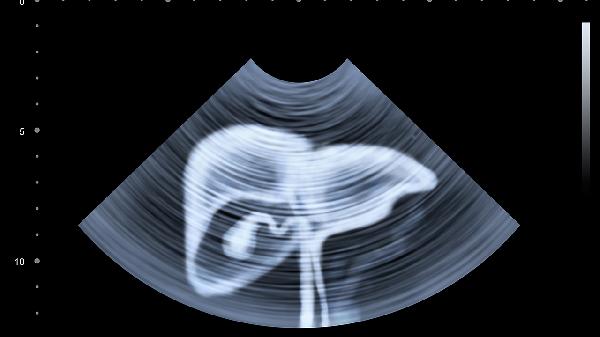

胆囊炎症会刺激胆汁分泌异常,导致右上腹持续性胀痛。多与高脂饮食有关,可能向右肩放射,伴随恶心呕吐。需进行超声检查确诊,急性发作期需禁食并静脉补液治疗。

肝脏炎症会导致肝包膜牵张,表现为右季肋区胀满感。常见于病毒性肝炎患者,伴随乏力、食欲减退。需检测肝功能指标,进行保肝治疗,避免饮酒和损肝药物。